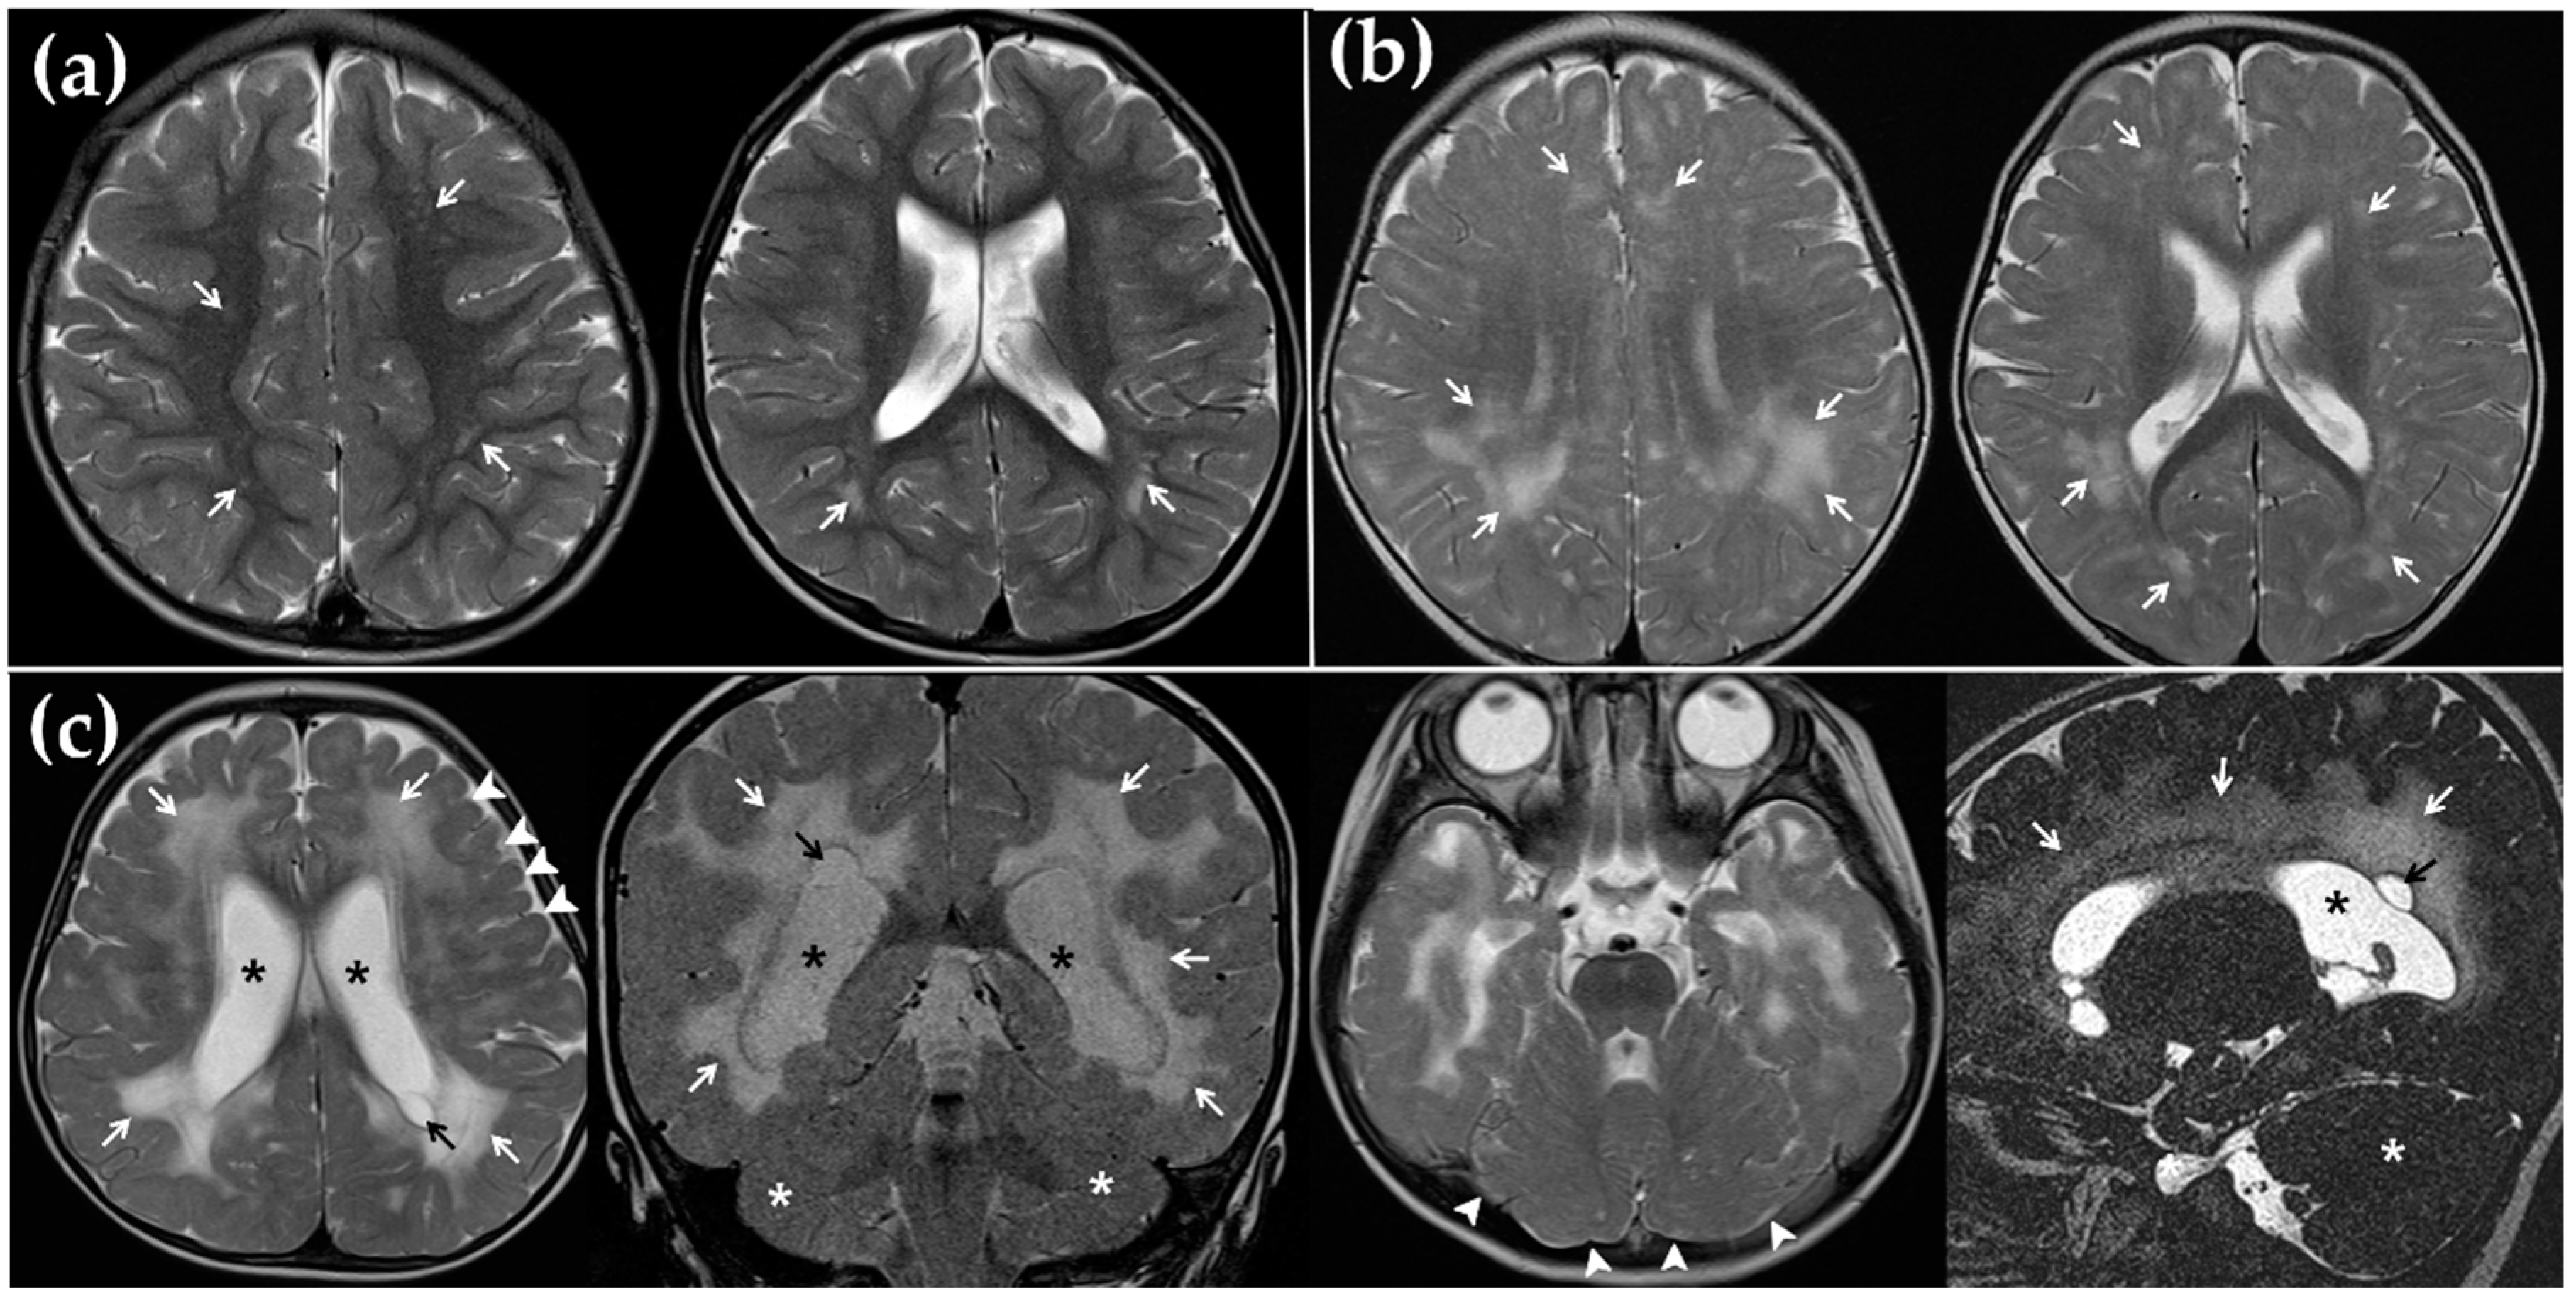

3.2. MRI Findings and Its Correlation with CI Outcome